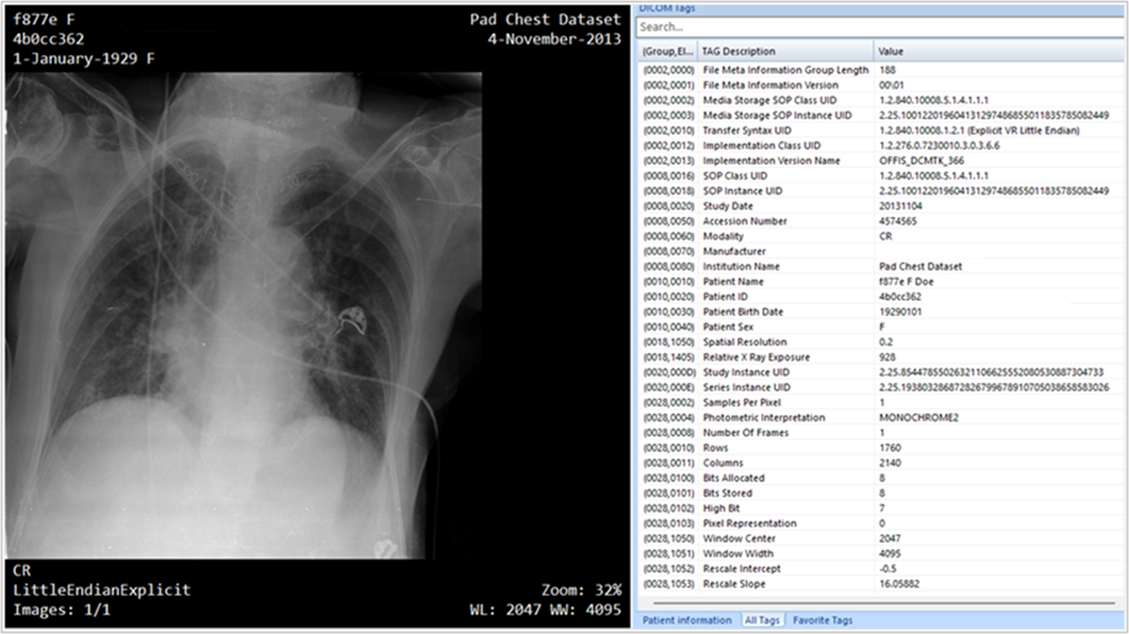

تعمل DICOM® على تحويل بيانات التصوير الطبي إلى بيانات منظمة قابلة للاستخدام، وفتح مستودعات البيانات، والسماح بالتشغيل التفاعلي بين الأنظمة المتوافقة. لقطة الشاشة التالية هي مثال على بيانات التصوير.